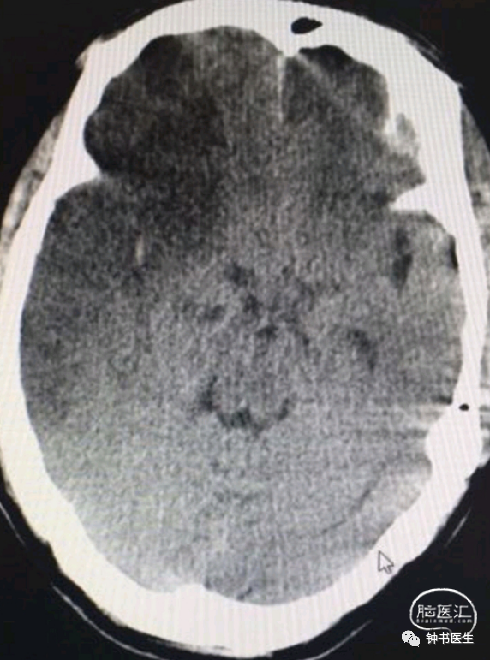

2019-1-10 当地CT

2019-1-12 当地CT

2019-1-12

2019-1-13

2019-1-14

2019-1-16

2019-1-19